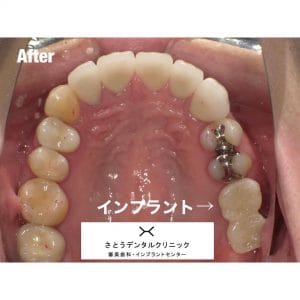

Case032

広島からの患者様です。

前歯を綺麗にしたい。インプラントをしたい。

という主訴で東京の歯医者をいろいろ調べて当院を選んでくださいました。

毎回、遠い中しっかり通ってくださり、選んで頂けた嬉しさと、その気持ちに応えたいという想いで診療させて頂きました。

前歯はご希望のお色でラミネートベニアでは出せない透明感のあるセラミックに上下左側7はインプラントをさせて頂きました。

左上は破折で温存不可。

骨も少なかったので、サイナスリフトも行い計五回の来院で被せ物を入れさせて頂きました。

左下は前回のクリニックでの埋入位置が深すぎて食べカスも毎回詰まる、セルフメンテナンスではら汚れも取れない。インプラント周囲炎にもなっていたので、一度前のインプラントを除去し、そこから新しくインプラントを埋入し、診療させて頂きました。

インプラント、歯並び、審美歯科にご興味のある方はいつでも相談にお越しください。

担当 理事長 佐藤 悠野